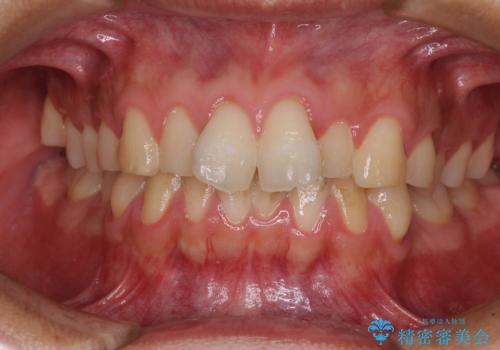

捻れて飛び出した前歯 インビザラインで整った前歯に

- 上下前歯のデコボコと、それに伴う出っ歯を気にして来院された患者様です。

インビザラインによる上下歯列の側方拡大と後方移動、IPR(歯と歯の間を削る)にるスペースの獲得により歯列を整えることとしました。